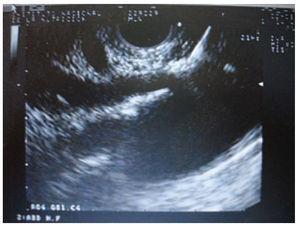

Materials and methodsIn a retrospective analysis of data obtained prospectively the records of patients with pain caused by pancreatic cancer who underwent EUS CPN at the Instituto Nacional de Ciencias Médicas y Nutrición “Salvador Zubirán” from March 2005 to May 2007 were evaluated. All patients have unresectable pancreatic cancer confirmed by computed tomography (CT), magnetic resonance imaging (MRI) and/or EUS; EUS criteria and fine-needle aspiration (FNA) were used when a tissue diagnosis was not available before EUS. They underwent to EUS CPN during the same EUS procedure for diagnosis. Before the procedure all patients had laboratory tests including prothrombin time and full blood count. The patients were placed in left decubitus position and sedated by using a combination of midazolam, propofol and phentanyl by anesthetist. Patients were continually monitored with an automated noninvasive blood pressure device, electrocardiogram, and pulse oximetry throughout the procedure. EUS CPN was performed with a linear array echoendoscope GFUCT-140 (Olympus) by an experienced echoendoscopist. The angle formed by the aorta and celiac trunk was identi- fied through the posterior gastric wall. Under direct EUS visualization, a 22 gauge, 8 cm aspiration needle (Wilson-Cook Medical, Inc. Winston-Salem, N.C.) primed with normal saline solution was placed immediately adjacent and anterior to the aorta at the level of the celiac trunk (figure 1). After injecting 2 mL of saline solution to clear the needle, an aspiration test was performed, if no blood was obtained, 10 mL of 1% lidocaine was injected (figure 2). The aspiration test was repeated, and if no blood, 20 mL of dehydrated 98% absolute alcohol was injected. The needle was then flushed with 3 mL of saline solution and withdrawn from the patient. After the procedure a Doppler ultrasound of the celiac trunk and aorta was made to evaluate permeability. The average estimated time for the EUS CPN portion of the procedure was 10 minutes. After the procedure all patients remained under observation for at least 2 hours to rule out any complications. All patients were reevaluated for complications 7 days after the procedure. Dosage and class of pharmacologic treatment were evaluated before the procedure as well as 15 days and 30 days after procedure. Measurement of intensity of pain was made with a validated visual analog pain scale (0-10) in all patients6 by a pain specialist. Measurements two and four weeks after the procedure were made. The complications related to the EUS CPN were determined in agreement with the medical records. Medians, ranges and proportions were used to summarize the demographics and clinical variables. EUS CPN pain scores paired before and after (15 and 30 days) were compared with the Friedman test.

Figure 2. Injection of 1% lidocaine.